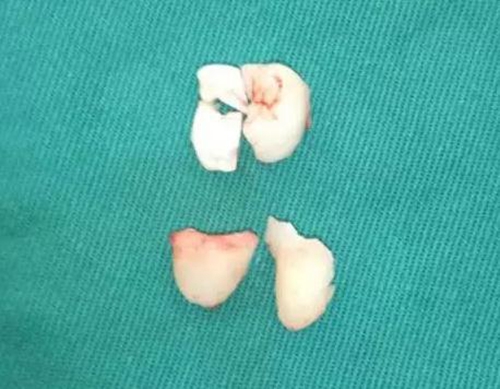

使用彎機(jī)加固美拔牙長(zhǎng)柄車針,沿冠邊緣去除遠(yuǎn)中及頰側(cè)骨,完全去骨后,用彎機(jī)沿冠正中線分牙,完全分開后,挺患牙,這時(shí)的48稍微有些動(dòng)度,但因近遠(yuǎn)中骨阻力較大,無法從遠(yuǎn)中向脫位。

使用普通手機(jī)加裂鉆沿遠(yuǎn)中冠中間磨除大部分冠組織,取出。

使用彎機(jī)開始分殘冠,使牙根近遠(yuǎn)中向的分開,使用牙挺挺松后,取出遠(yuǎn)中根。

去冠近中的骨壁,挺出之前分離出的殘冠,分次取出近中牙根,取刮匙刮牙槽窩。探查是否有剩余牙體組織。